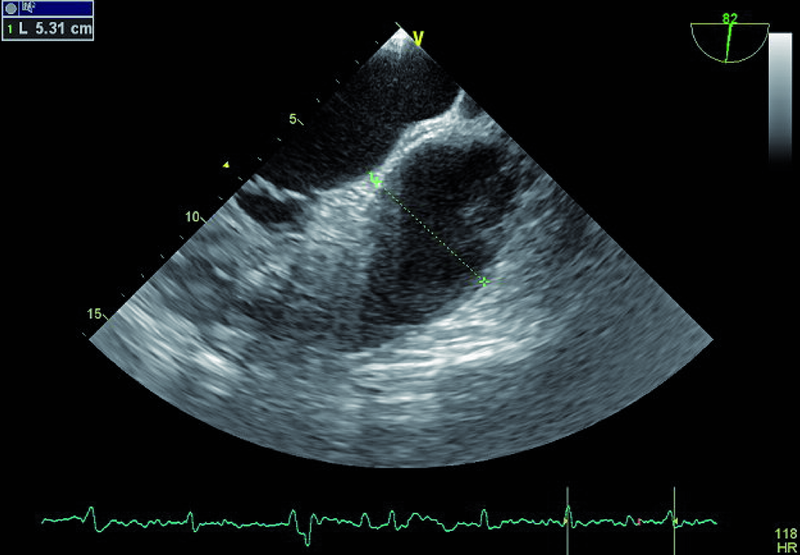

Kobieta, lat 73. Jakie patologie można rozpoznać na rycinach?

6. Poszerzenie pnia tętnicy płucnej (ryc. 4).